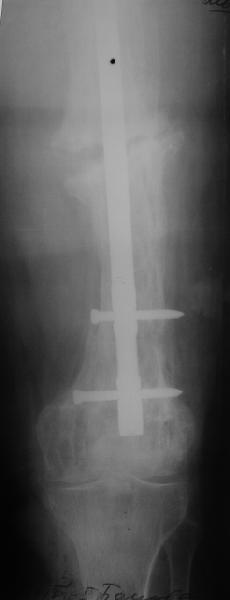

Еще один пример. Пациентка с юга России, прислала рентгенограммы через

год. На сегодня прошло 2 г. 8 мес. после операции. Несмотря на не очень

убедительный процесс сращения, пациентка ходит. Учитывая остеопороз при

Педжете, решили, что динамизировать вообще не нужно.